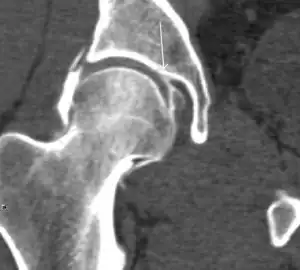

Synovial chondromatosis can be confidently diagnosed by X-ray when calcified cartilaginous chondromas are seen. However, other synovial proliferative processes, such as pigmented villonodular synovitis, require MRI for accurate diagnosis, although noncalcified synovitis can be suspected in radiographs by indirect signs, such as soft tissue swelling and/or erosions in the femoral head, femoral neck, or acetabulum (Figure 7).[1]

Figure 7:

-

Axial CT image of pigmented villonodular synovitis eroding the posterior cortex of the femoral neck.[1] -

Sagittal T2* gradient echo image showing a posterior soft tissue mass with hypointense areas secondary to hemosiderin deposition.[1] -

X-ray of synovial chondromatosis.[1] -

CT of synovial chondromatosis.[1]

In synovial proliferative disorders, MRI demonstrates synovial hypertrophy. In the case of PVNS, characteristic foci of low signal intensity related to hemosiderin deposition are better seen on gradient echo T2* images (Figure 7). In the case of synovial osteochondromatosis, the synovial hypertrophy is accompanied by intermediate signal cartilaginous loose bodies and/or low signal calcified loose bodies.[1]